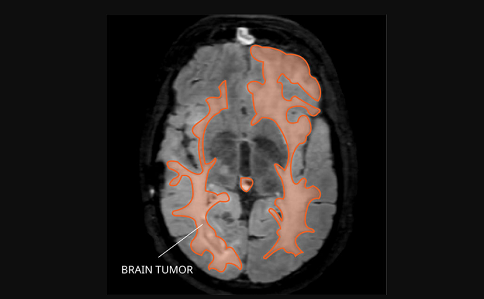

腦膠質(zhì)瘤是常見(jiàn)的惡性腦腫瘤,一旦發(fā)展到晚期,患者的癥狀將會(huì)變重,治療也比較困難。晚期腦膠質(zhì)瘤患者和家屬對(duì)能活多久這個(gè)問(wèn)題比較關(guān)注。不同類型的膠質(zhì)瘤治療方法不同,生存期也有所不同。那么晚期腦膠質(zhì)瘤能活多久,如何延長(zhǎng)晚期患者的生存期呢?

圖源:美國(guó)國(guó)立癌癥研究所